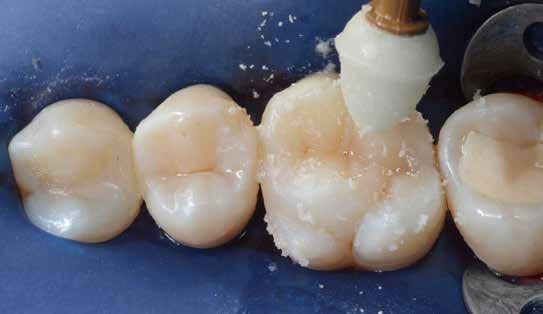

KOMPOZIT RÉTEGEZÉS

A restauráció nagy részének újraalkotásához kromatikus mikrohibridet (Renamel Microhybrid, Cosmedent) – ebben a példában az A1-es árnyalatot – használtunk. A mikrohibrid a teljes palatális oldalt fogja alkotni, és az arc felőli oldalon az átmeneti zóna ferde részének teljes egészét le kell fednie. Nem tanácsos, hogy a mikrohibrid túlmenjen a chamfer szélén, mert akkor nem marad hely a mikrotöltött kompozit számára, és a restauráció ezen része idővel tompának tűnhet, amely optikai diszharmóniát okozhat.

Ne feledje, hogy ha a chamfer nincs teljesen lefedve, a törés továbbra is látható lehet. Szükség esetén folyékony opakert lehet hozzáadni a törésvonal további elfedésére. Így jön létre az „üres vászon”. A felesleg vagy az okklúzió ezen a ponton beállítható. Ez szárazon történik, majd a restaurációra töltetlen gyanta (Complete Unfilled Resin, Cosmedent) kerül. A 11. ábra a behelyezett és beállított mikrohibridet mutatja. Mivel a szomszédos központi metszőfogon nagy mennyiségű metszőfog-transzlucencia, valamint egy kiemelkedő metsző-

fog-halo volt, egy vékony, éles szondával (Matt’s Probe) szürke színt (Creative Color, Cosmedent) helyeztünk a metszőfog harmadára, ügyelve arra, hogy elkerüljük a metszőfog szélét (12. ábra). A mikrohibrid eredendő opacitása gyakran szolgálhat a fog szélén a metszőfogak halójaként, bár ha szükséges, a metszőfogak halóját tovább lehet fokozni folyékony opakkerrel. Ebben az esetben a fehér és A1 opaquer 50/50 arányú kombinációját egy gyantatartóban keverve, a szonda segítségével vittük fel az incisalis szélre (13. ábra). A 14. ábra a mikrohibrid kompozit felett a kikeményített árnyalatok és opakkerek hatását mutatja, amely polikromatikus hatást mutat. A tinták és opakok metsző hatásának fokozása és a tartós fényezés érdekében kis mennyiségű achromatikus mikrotöltésű kompozitot (Light Incisal, Cosmedent) helyeztek fel végső rétegként. A kompozitnak el kell fednie a lánggyémánt által létrehozott végtelenített ferdeséget, és csak a restauráció arcfelületére kell kerülnie, nem helyezhető el semmilyen okklúziós területre. A 15. ábra a felhelyezett, formázott mikrotöltött kompozitot szemlélteti. (Kromatikus kompozit is használható, ha a metszéshatás nem kifejezett.) Korongok és polírozók kombinációjával a restaurációt a szomszédos fog utánzása érdekében befejezték (16. ábra).